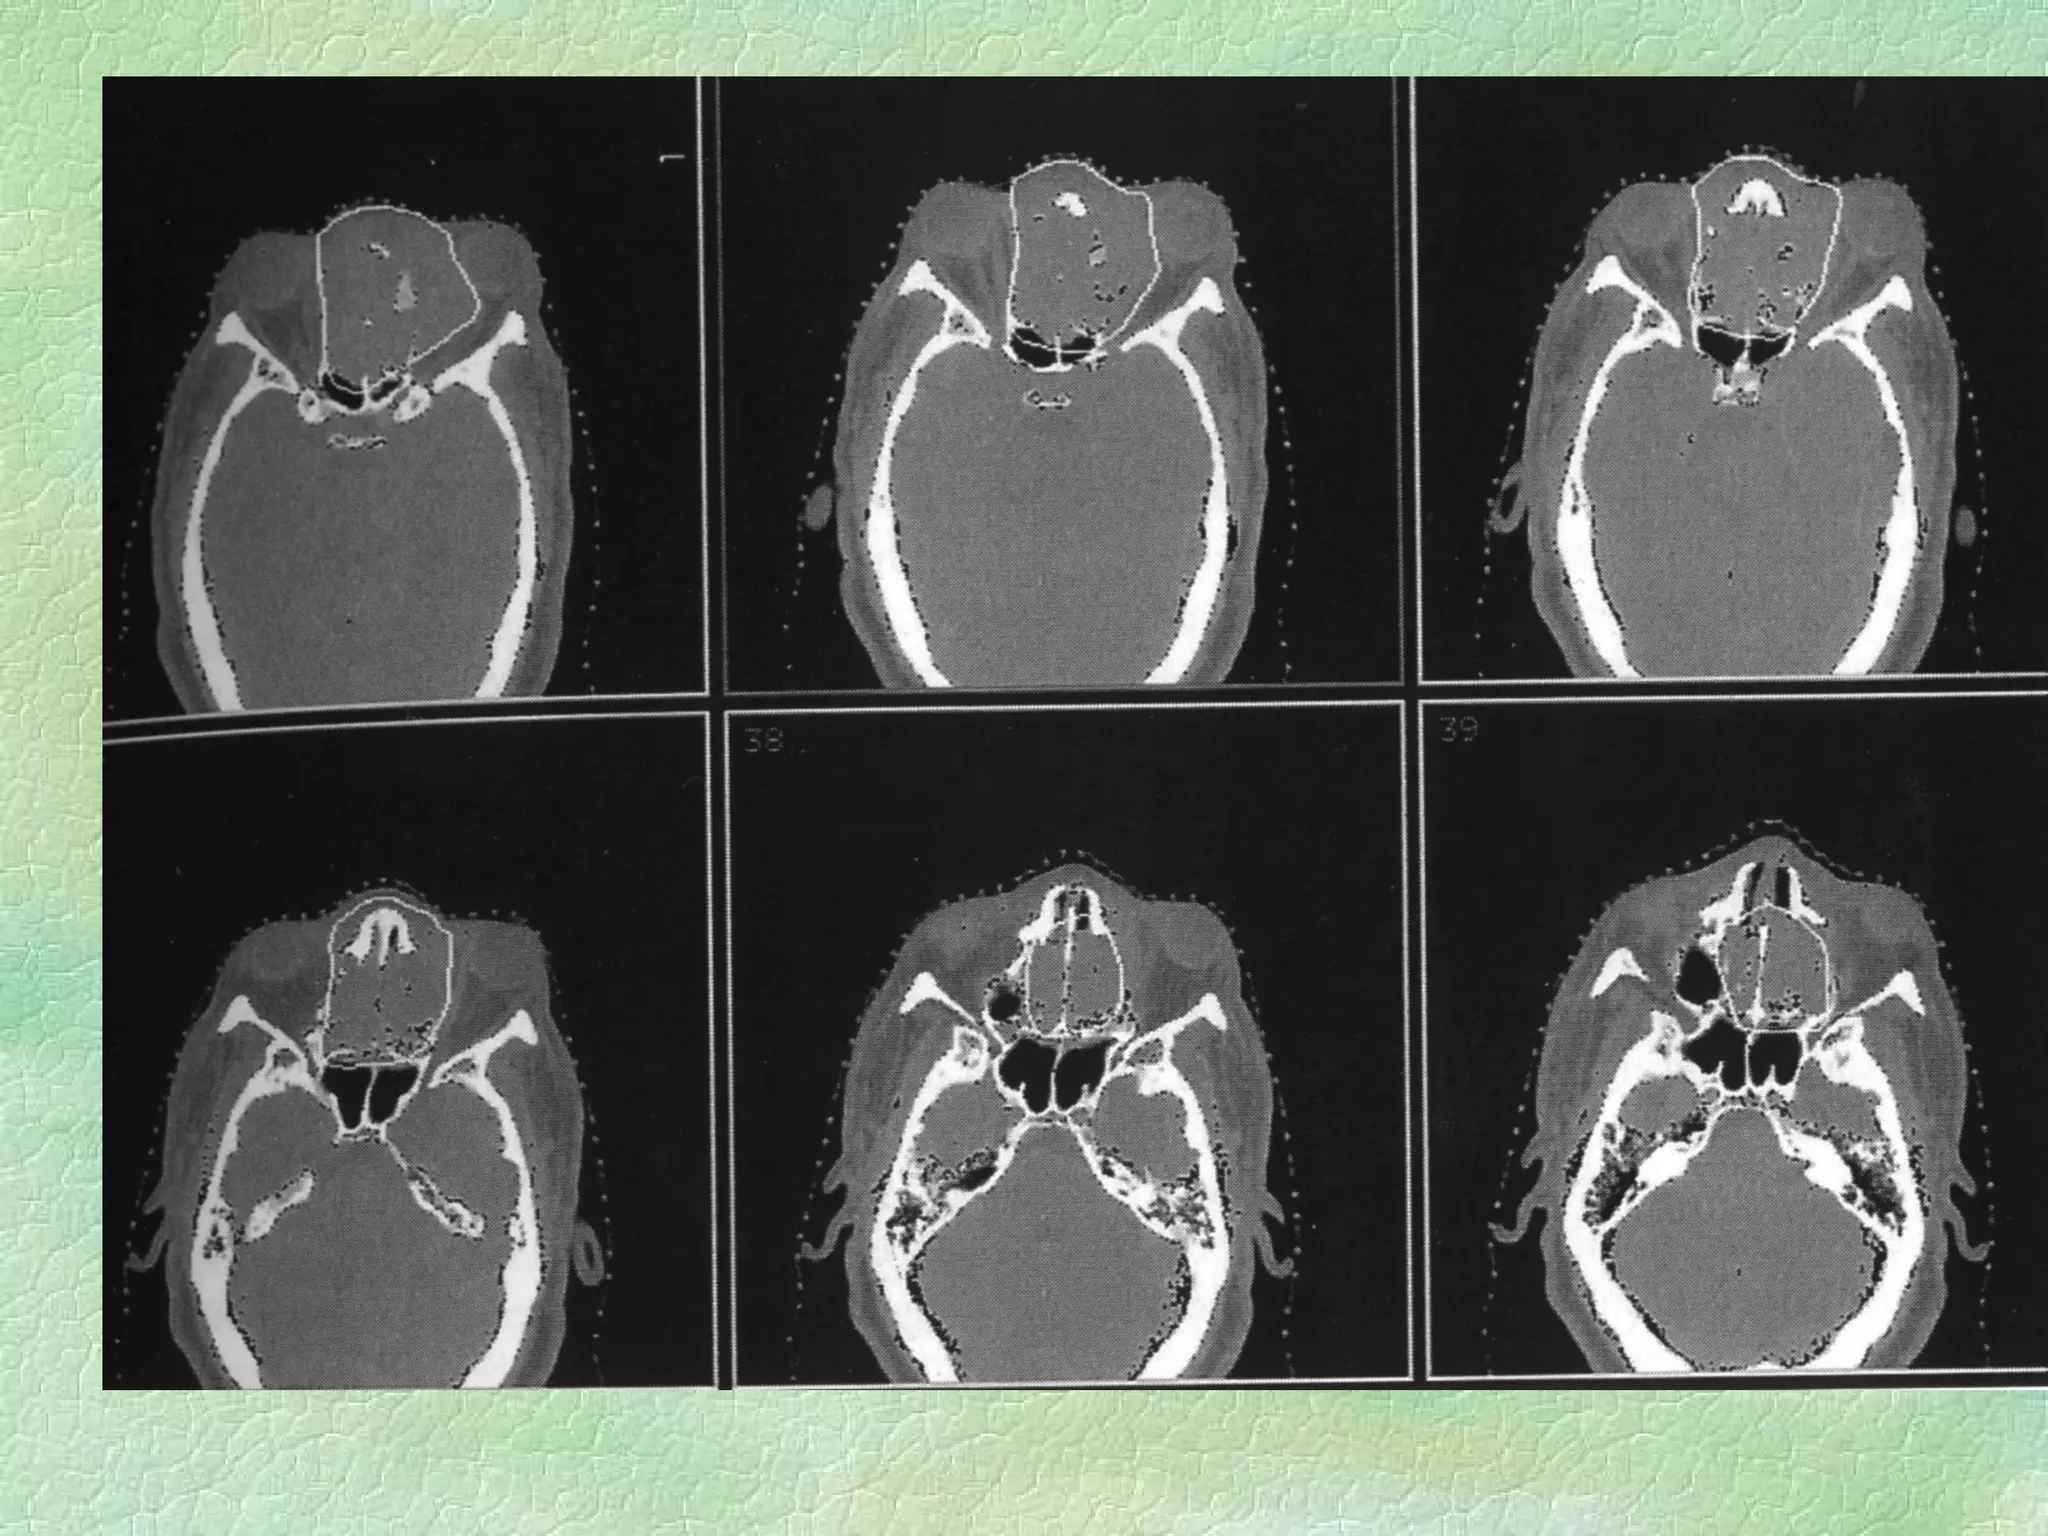

Virtual Simulation: -  Immobilization CT Coordinate system Structure Delineation Isocentre localization Beam placement/definition